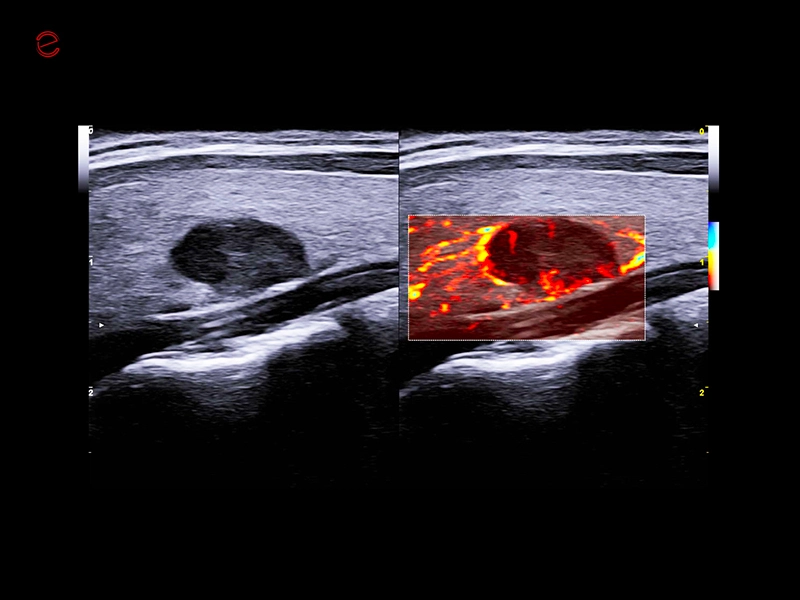

MyLab™C25 - Mioma PD

MyLab™C25 - Mioma PD